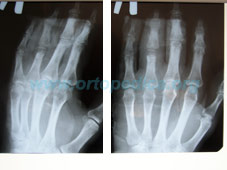

Рентгенограмма до операции - деформация сустава 4 пальца кисти, наличие фиксаторов после предадущей операции |